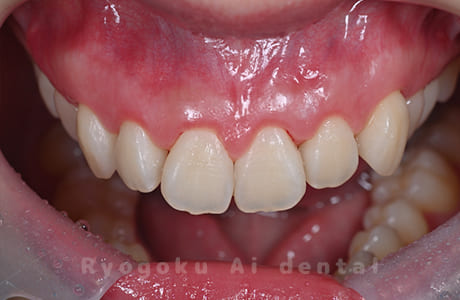

Case01

- 原因

- ガミースマイル

- 治療回数

- 1回

- 治療期間

- 術後治癒も含めて約1か月

- 治療内容

- ガミースマイル改善治療

- 治療費用

- 121,000円

(1ブロックあたり、6前歯部分)

笑った時に歯茎が見えてしまうガミースマイルを改善したいとのことでご来院された患者様です。術後も大変満足していただきました。